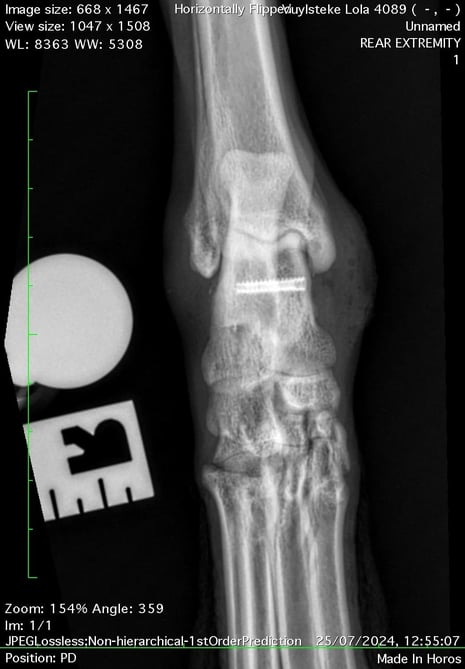

Intra-operative radiographs of the talus repair

Postoperatively, Lola’s limb was supported in a bandage for an additional six weeks to protect the repair. At recheck, CT scans confirmed good healing progress, and the bandage was removed. Just two weeks later, Lola had returned to full activity, completely sound.